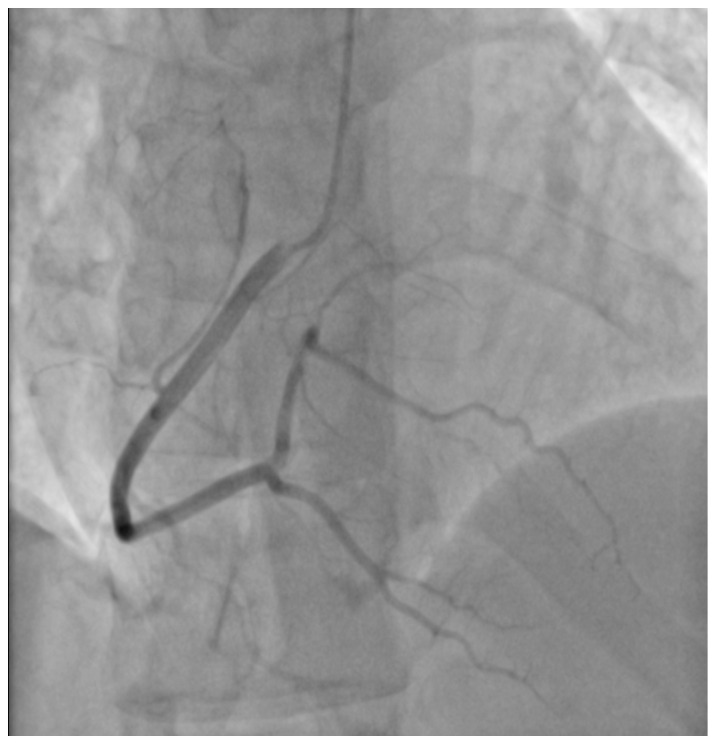

A 29-year-old male patient, a manual worker without history of overt infectious myocarditis, without classic risk factors for cardiovascular diseases, with mixed anxiety and depressive disorder, was treated with prescribed off-label medical marijuana (delta-9-tetrahydrocannabinol THC 19% and cannabidiol CBD < 1%, bred from Lemon Skunk Cannabis Strain in the form of unprocessed dried leaves) for around 3 years, smoked at least 3–4 times a day and was diagnosed with severe cannabis use disorder (continued use of cannabis despite clinically significant impairment) [ref. 6]. It was diagnosed by a psychiatrist according to the fifth version of the Diagnostic and Statistical Manual of Mental Disorders (DSM-5) with 8 out of 11 criteria met: hazardous use, social/interpersonal problems, neglected major roles, withdrawal, used larger amounts/longer, much time spent using, activities given up and craving [ref. 7]. Moreover, the patient was categorized as a chronic user [ref. 8]. He had been suffering from paroxysmal hemodynamically unstable ventricular tachycardia (VT). The first episode occurred 30 months ago and the patient was referred from an emergency room to a distant cardiology center, where upon coronarography, apart from myocardial bridge localized in the middle segment of the left anterior descending coronary artery no lesions in the coronary arteries were recorded. There were no specific abnormalities recognized in resting ECG (Figure 1, left panel). In the echocardiogram the structure and function of the heart was normal, apart from a mildly compromised left ventricular systolic function with left ventricular ejection fraction (LVEF) of 43%. At that time the patient did not consent to the proposed diagnostics of VT consisting of cardiovascular magnetic resonance imaging of the heart, electrophysiological study, genetic testing and therapy with subcutaneous implantable cardioverter-defibrillator. He received metoprolol in extended-release drug formulation (metoprolol succinate) of 25 mg q.d. due to intolerance of higher doses, potassium, magnesium and vitamin B6 supplementation. Within this period, the subject experienced at least six episodes of VT that required medical assistance. Moreover, 7 months earlier he was admitted to the catheterization unit again after an acute episode of retrosternal pain following marijuana intake. Once more, no lesions within the coronary arteries were observed in coronarography (Figure 2 and Figure 3). ECG showed no signs of ischemia, echocardiography was without segmental dysfunction of cardiac muscle, and LVEF equaled 40%. Noteworthy, the top troponin T serum concentration exceeded the upper end of the scale (>10,000 ng/mL), with CPK of 4167 U/L, CK-MB-428 U/L and CRP 3.4 mg/L. Non-ST-elevation myocardial infarction was diagnosed but the patient still declined extended diagnostics and marijuana addiction therapy. The treatment was supplemented with acetylsalicylic acid 75 mg q.d., clopidogrel 75 mg q.d., ramipril 1.25 mg q.d., rosuvastatin 10 mg q.d., eplerenone 25 mg q.d. and pantoprazole 20 mg q.d.